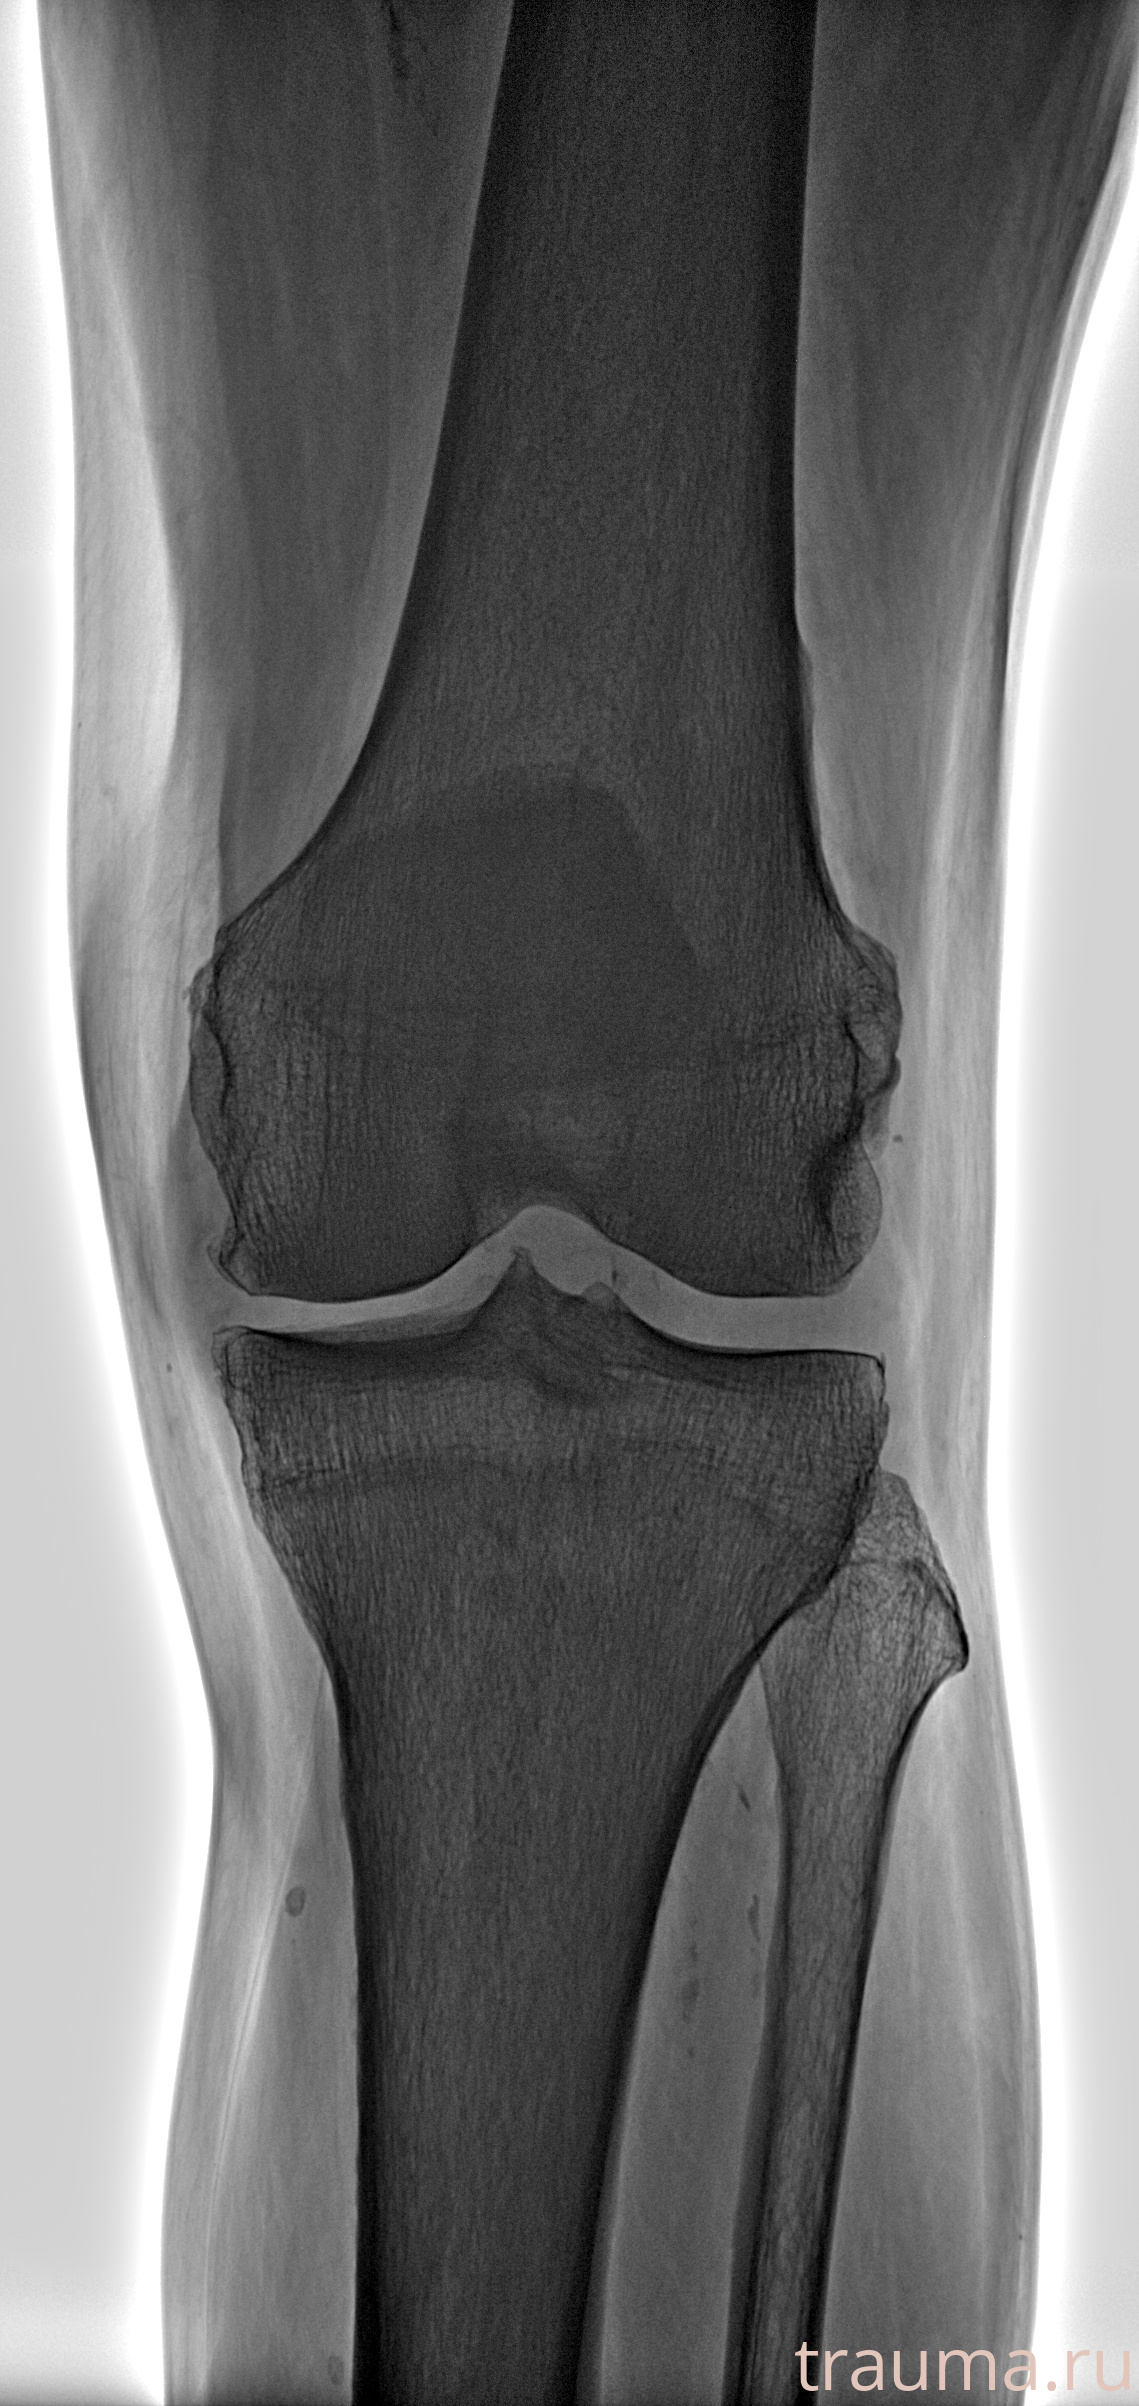

Рентгенограммы

Рентген на дому: по вашему адресу приезжает врач-рентгенолог, травматолог-ортопед с мобильным рентгеновским аппаратом, проводит диагностику травмы или заболевания, делает необходимые рентгенограммы, дает рекомендации по дальнейшему лечению. Получить качественные снимки в домашних условиях возможно благодаря уникальной методике, разработанной МосРентген Центром для института  Склифосовского